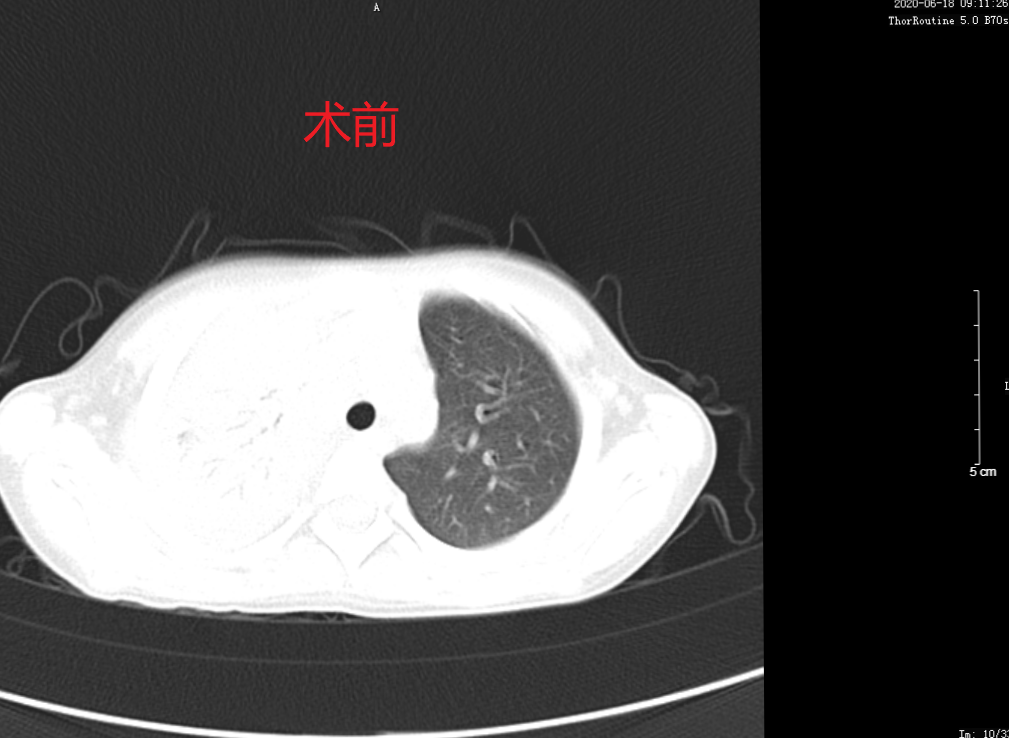

本次支气管镜术在PICU(儿童重症监护室)内密切监护的条件下,进行局麻镇静,使患儿安静睡眠后行支气管镜检查,支气管镜经右鼻腔进入肺部进行治疗,整个操作过程顺利,患儿无不良反应,病情平稳。术后两天患儿咳嗽症状消失,第3天复查胸部CT病灶较前明显吸收,疗效显著。

术前患儿胸部CT